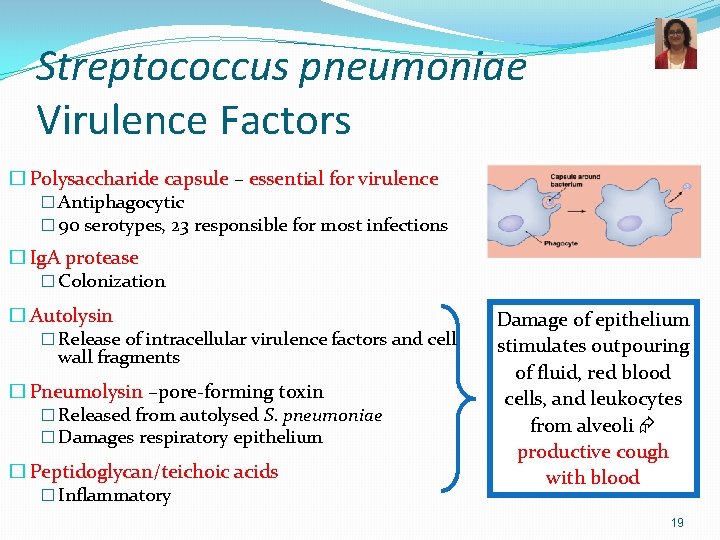

Streptococcus pneumoniae Virulence Factors � Polysaccharide capsule – essential for virulence � Antiphagocytic � 90 serotypes, 23 responsible for most infections � Ig. A protease � Colonization � Autolysin � Release of intracellular virulence factors and cell wall fragments � Pneumolysin –pore-forming toxin � Released from autolysed S. pneumoniae � Damages respiratory epithelium � Peptidoglycan/teichoic acids � Inflammatory Damage of epithelium stimulates outpouring of fluid, red blood cells, and leukocytes from alveoli productive cough with blood 19

Pneumococcal Pneumonia: Typical Lobar Pneumonia �Fever with shaking chills �Productive cough with blood tinged sputum (rusty sputum) �Chest pain, shortness of breath �fatigue 20